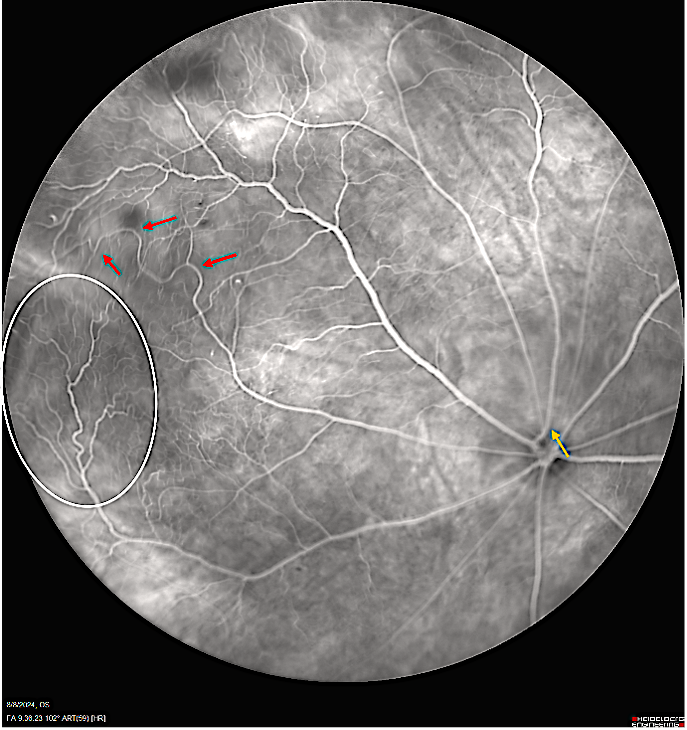

When infants are born prematurely, a host of serious health issues can occur. One of those issues is retinopathy of prematurity (ROP): an eye disorder and loss of vision that can quickly progress.

To build a diagnostic tool, Kang-Mieler and Gan will do something remarkable: create their own expert dataset of what ROP pathology should look like in medical imaging, in order to train an AI how to find it most accurately.

To surmount that challenge, Kang-Mieler and Gan will work with Stevens post-doctoral fellows and graduate and undergraduate student teams to collect animal ROP images and process them, extracting the most useful predictive features from the images, then using them to teach an AI model to generate the best-possible “synthetic” images of human ROP by employing generative AI image-translation techniques.

This new, synthetic image data can then be used to train neural networks that will assist ophthalmologists in spotting ROP or tracking the progression of the disease.

“One strength of our approach is that we have good data on the progression of ROP through the lifetime of animals, from its emergence to development,” adds Kang-Mieler. “That has been captured pretty robustly in the imagery. If we can successfully utilize this information for human health prediction, it could benefit thousands of prematurely born infants.”